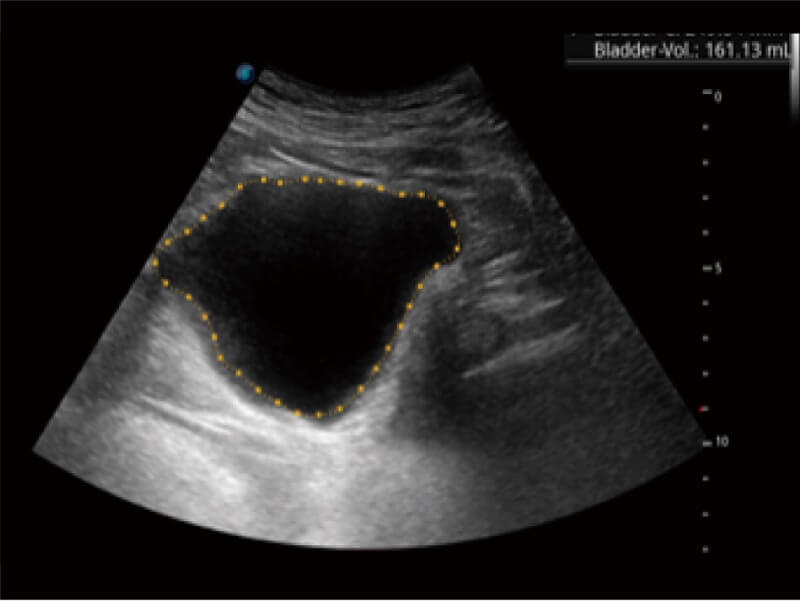

Die zentrale Verfolgung der Blasenwand und die Volumenmessung mittels Auto Bladder kann effizient genauere Konturen und Ergebnisse liefern, die nicht von Form und Größe der Harnblase abhängen.